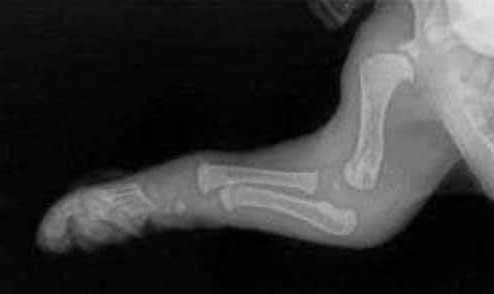

Ectrodactyly

Ectrodactyly* is an extremely rare congenital malformation in which the development of the dog's paw bone (mesenchymal) cells are interrupted during gestation. Causes could include genetic mutations, environmental factors such as maternal disease or diet, drugs, vaccines, or radiation. Ectrodactyly often is displayed as a cleft between metacarpal bones, usually the first and second metacarpal bones. They may be abnormally formed or missing. In a 2017 case of a cavalier King Charles spaniel puppy in New Zealand, both forelegs are affected, with one shorter than the other and resembling a lobster claw and the other with a split between the toes. (See photo at right.)

* Also known as split-hand deformity or lobster syndrome.